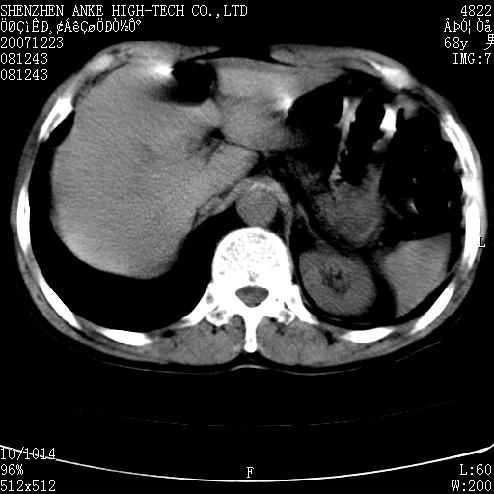

患者:男,63岁,2年前胆囊切除术后,现右上腹部剧烈疼痛近2天.

有无外伤史?右肾包膜下血肿可疑。

主要是问右肾有没有问题?患者无明显外伤史.

未见异常,病人差闭气,伪影较多.

肠管积气明显.

肠道准备不好,干扰影大。

肠道气体伪影干扰太大了,应该是干扰所致,未见明显异常。

肠道准备不好,胃底后壁显示不清,右肾改变考虑为伪影。

上腹部ct平扫未见明显异常。(肠道气体较多,患者呼吸了)

请看第一张正位片,胸主动脉象有扩张,胸主动脉瘤?